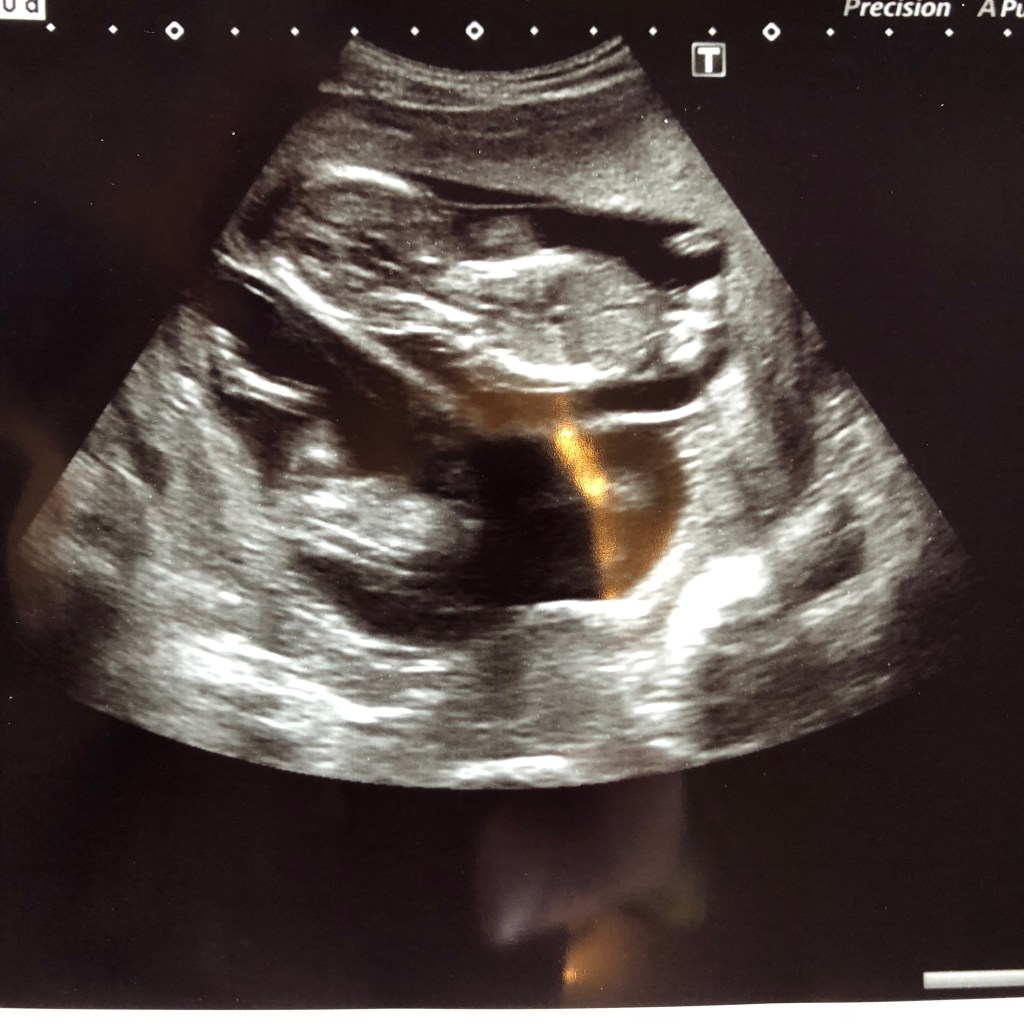

Kaksi vuotta sitten juuri näihin aikoihin saimme tietää että odotamme kaksosia. Itkin ja nauroin hysteerisesti yht’aikaa kun se tieto tuli. Kätilö ojensi minulle nenäliinoja. En yleensä ole kauhean hysteerinen, mutta raskaushormonit saavat tunteet pintaan ihan eri tavalla. Kun hetken pyydettiin että odottaisin odotusaulassa, soitin heti miehelleni. Hän oli metsästysreissussa Ruotsissa. Melkein kiljuin puhelimeen. Siellä on kaksi! Onneksi olin siirtynyt käytävälle, kun odotusaula oli täynä ihmisiä ja siellä oli aivain hiljaista. Jokainen tuijotti johonkin ja yritti kuluttaa aikaa. Jotenkin se tuntui niin uskomattomalta. Hirvitti ja innosti ja jännitti. Oli kuin olisimme voittaneet lotossa. Aivan pieni etiäinen minulla oli. Niin paha se pahoinvointi oli. Oli päiviä etten kunnolla selvinnyt sängystä ja mietin välillä että pitäisikö tippa laittaa mutta sitten kuitenkin sen verran helpotti hetkeksi. Vedin peiton pään yli ettei hajut minua saavuta ja tutkin netistä tietoa HCG-hormonin pitoisuudesta. Epäilin että minulla olisi suuremmat pitoisuudet tällä kertaa. Nimittäin se on juuri se HCG-hormoni joka voi aiheuttaa pahoinvointia. Yksi mahdollinen selitys tähän oli, oli monikkoraskaus. En tietenkään heti uskaltanut tämmöistä vaihtoehto uskoa, niin harvinaista se on. (noin 1,4% synnytyksistä Suomessa on monikkosynnytyksiä eli kaksosia on noin 600-700 ja kolmosia on vain 5-10 (Suomen monikko ry)) Minun ja meidän onni oli että pahoinvointi pikkuhiljaa väistyi.